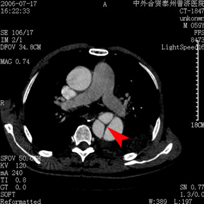

右心導管檢查:經股靜脈插入導管進入右心房、右心室再進入主動脈,亦可在右心房內通過卵圓孔未閉進入左心房再經左心室進入肺動脈。右心室收縮壓接近體循環壓力,主動脈內血氧飽和度低。

右心室造影:主動脈立即顯影,如有室間隔缺損,不但可顯示其大小和位置,而且左心室及肺動脈也同時顯影。